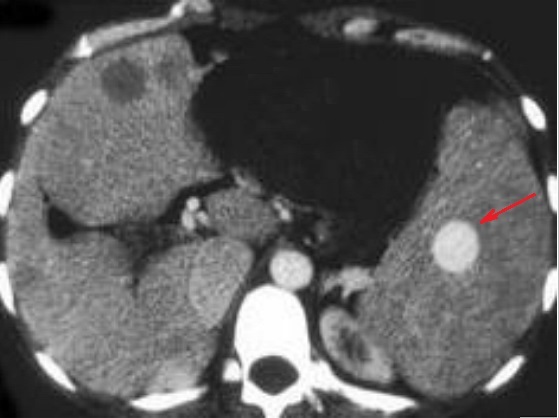

Image radiologique

TDM d'une hemangiome à aspect de masse arrondie (

fleche rouge ) hyperdense , homogène rehausse apres

injection de contrast intraveineuse , phase

arterielle . Image TDM plus C+ en coupe axial . |